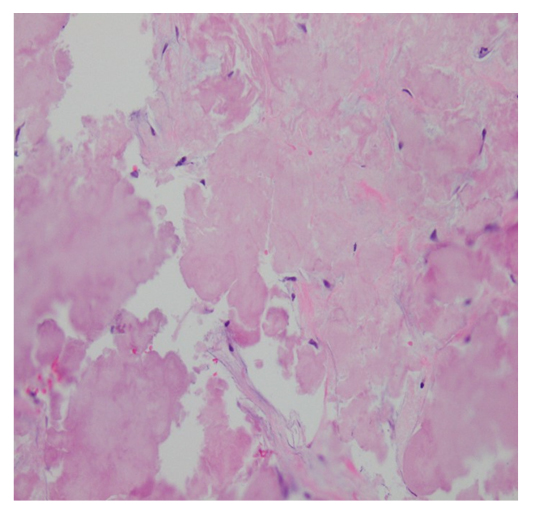

On presentation, initial lab work revealed normal levels of haemoglobin, creatinine, calcium, and serum protein. MRI of the lumbar spine revealed an irregular expansile enhancing soft tissue mass along the right hemisacrum from the S1 to S4–S5 level, encompassing the right neural foramina of S2, S3, and S4 (Figure 1). These findings were identical to the CT scan finding carried out 2 months previously. Furthermore, serum immunoglobulin, serum protein electrophoresis, urine protein electrophoresis, and free light chain ratio were also normal (Table 1). A PET scan was carried out 1 month prior to the presentation, and did not show FDG uptake or evidence of metastasis in the area. With these findings, the suspicion of MM, plasmacytoma recurrence, and malignancies were low, leaving a suspicion for a sacral amyloidoma (SaA) as the diagnosis of exclusion. CT-guided biopsy was performed, which revealed a proteinaceous material showing apple-green birefringence under polarised light following Congo red stain, without evidence of plasma cell neoplasm, consistent with SaA (Figure 2). This was unlike the biopsy which occurred 10 months prior, at the time of initial diagnosis, which showed sheets of mature-appearing plasma cells. Furthermore, a colonoscopy with biopsy and cardiac MRI were also done, which ruled out systemic amyloidosis.

Figure 2: Biopsy showing proteinaceous material with no evidence of neoplastic plasma cells.